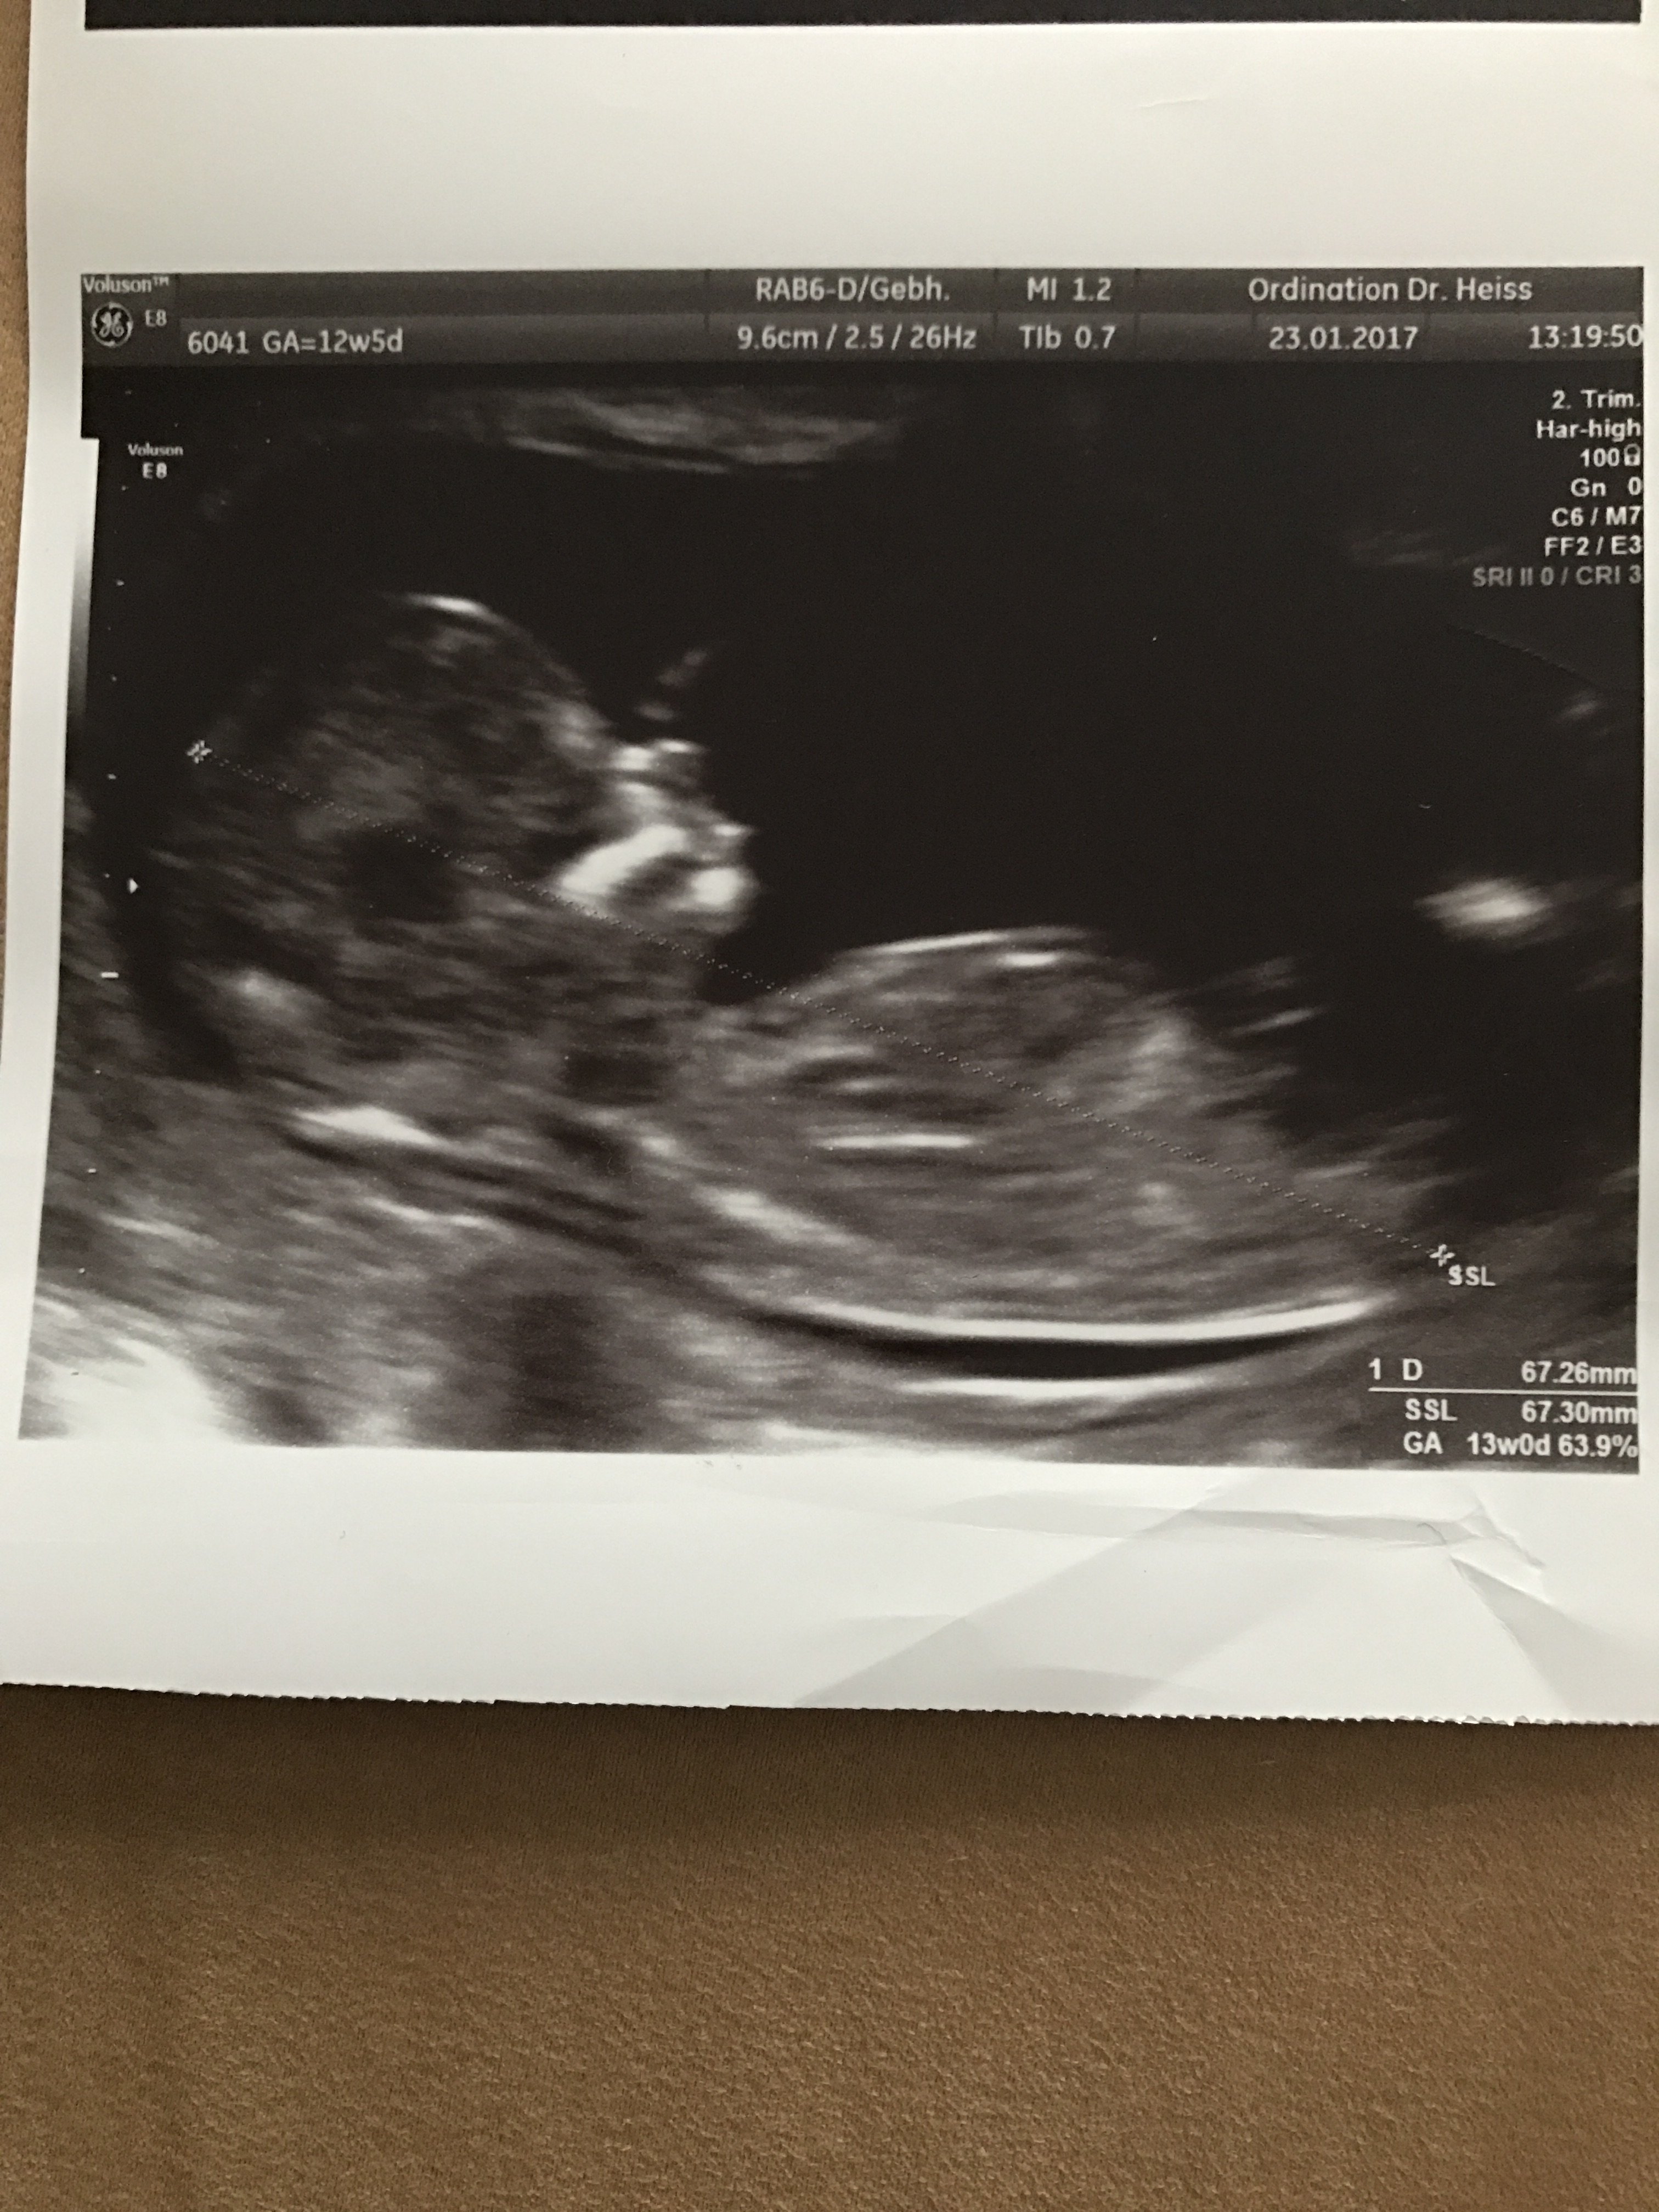

AlyaYahya61 Yeni Üye Üye 27 Şubat 2017 #199 Merhabalar Rica etsem arkadaşım için yorumlayabilirmisiniz?